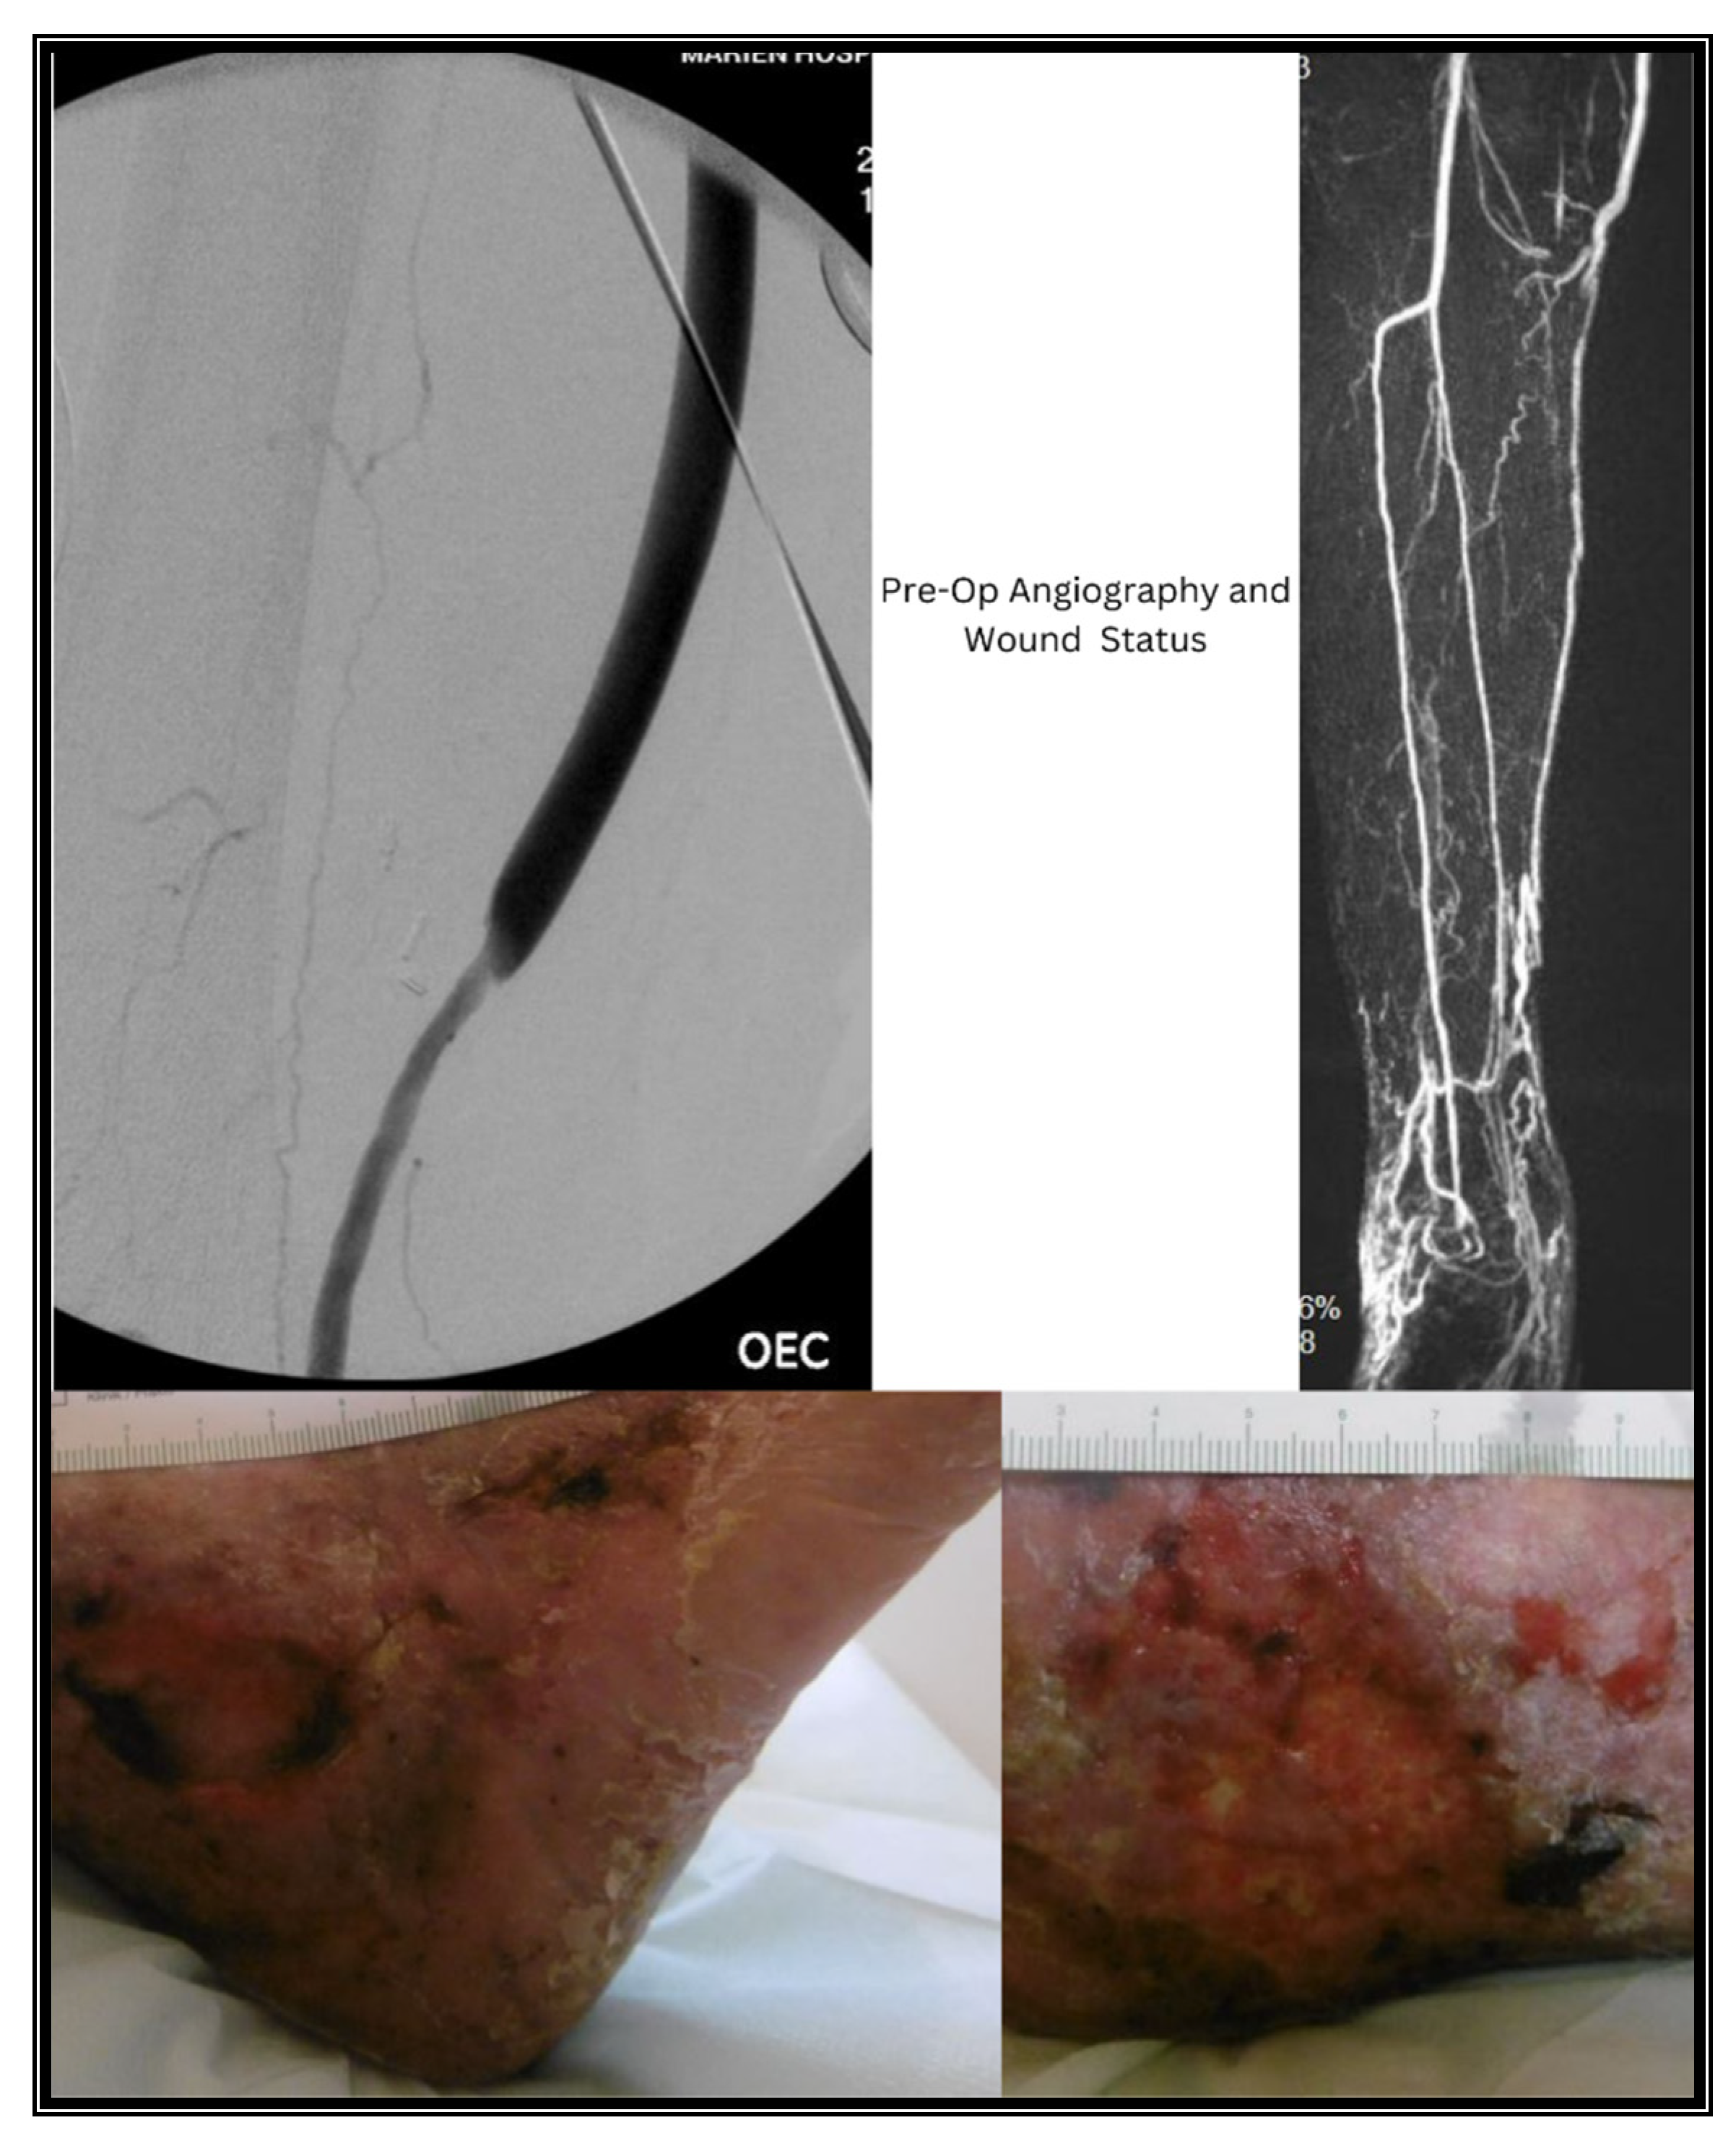

3.2. Case II